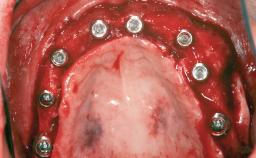

A 47-year-old woman who had suffered from aggressive periodontitis requiring a number of periodontal interventions over more than 10 years was referred by her general dental practitioner and periodontologist for bone augmentation and implant therapy. Her failing dentition had already been scheduled for extraction. The patient expressed a desire for implant-supported fixed restorations and esthetic improvement of her lower face. She had agreed to consult with a maxillofacial surgeon after the referring dentist had suggested bone augmentation. An initial examination by the maxillofacial surgeon revealed mobility of all residual teeth in a patient who was very unhappy with the function of her removable partial dentures. Due to periodontally migrated flaring teeth and loss of occlusal support, the vertical dimension of occlusion was dramatically reduced. The patient was displeased with her lower face because of deepened nasolabial, commissural, and supramental folds.

# of Implants 14

Bone Augmentation Horizontal|Sinus Floor Elevation|Staged|Vertical